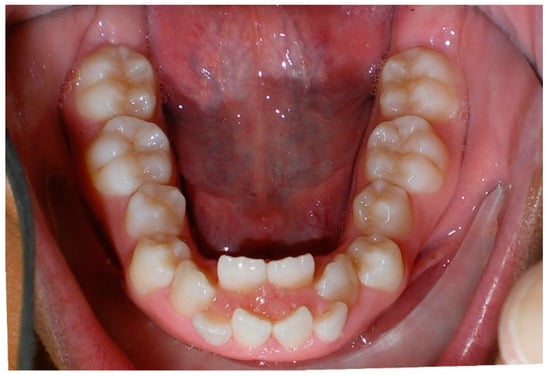

- Evaluation of buccal and lingual cortical plates: Figure 5, Figure 6 and Figure 7 show a case in which the mandibular lateral incisors are positioned lingual to the central incisors. Both mandibular lateral incisors are adjacent to each other. Figure 5 shows and intraoral occlusal photos with retained deciduous mandibular lateral incisors. There was no way to evaluate the buccal and lingual cortical plates through conventional 2D panoramic, periapical or occlusal radiographs. Therefore, CBCT was acquired and collimated to the area of teeth in order to assess the relationship of the four mandibular incisors to the labial and lingual cortical plates as well as to the adjacent teeth. As Figure 6 and Figure 7 display, CBCT shows that all permanent mandibular incisors are sound. It is important to note that thin buccal and lingual cortical plates may not be seen via CBCT—this does not denote that they are not present. In other words, CBCT images may not show a clinically present thin buccal and lingual cortical plates. In this case, the diagnostic information obtained from CBCT is far more significant than the information obtained from any other radiographic imaging technique.